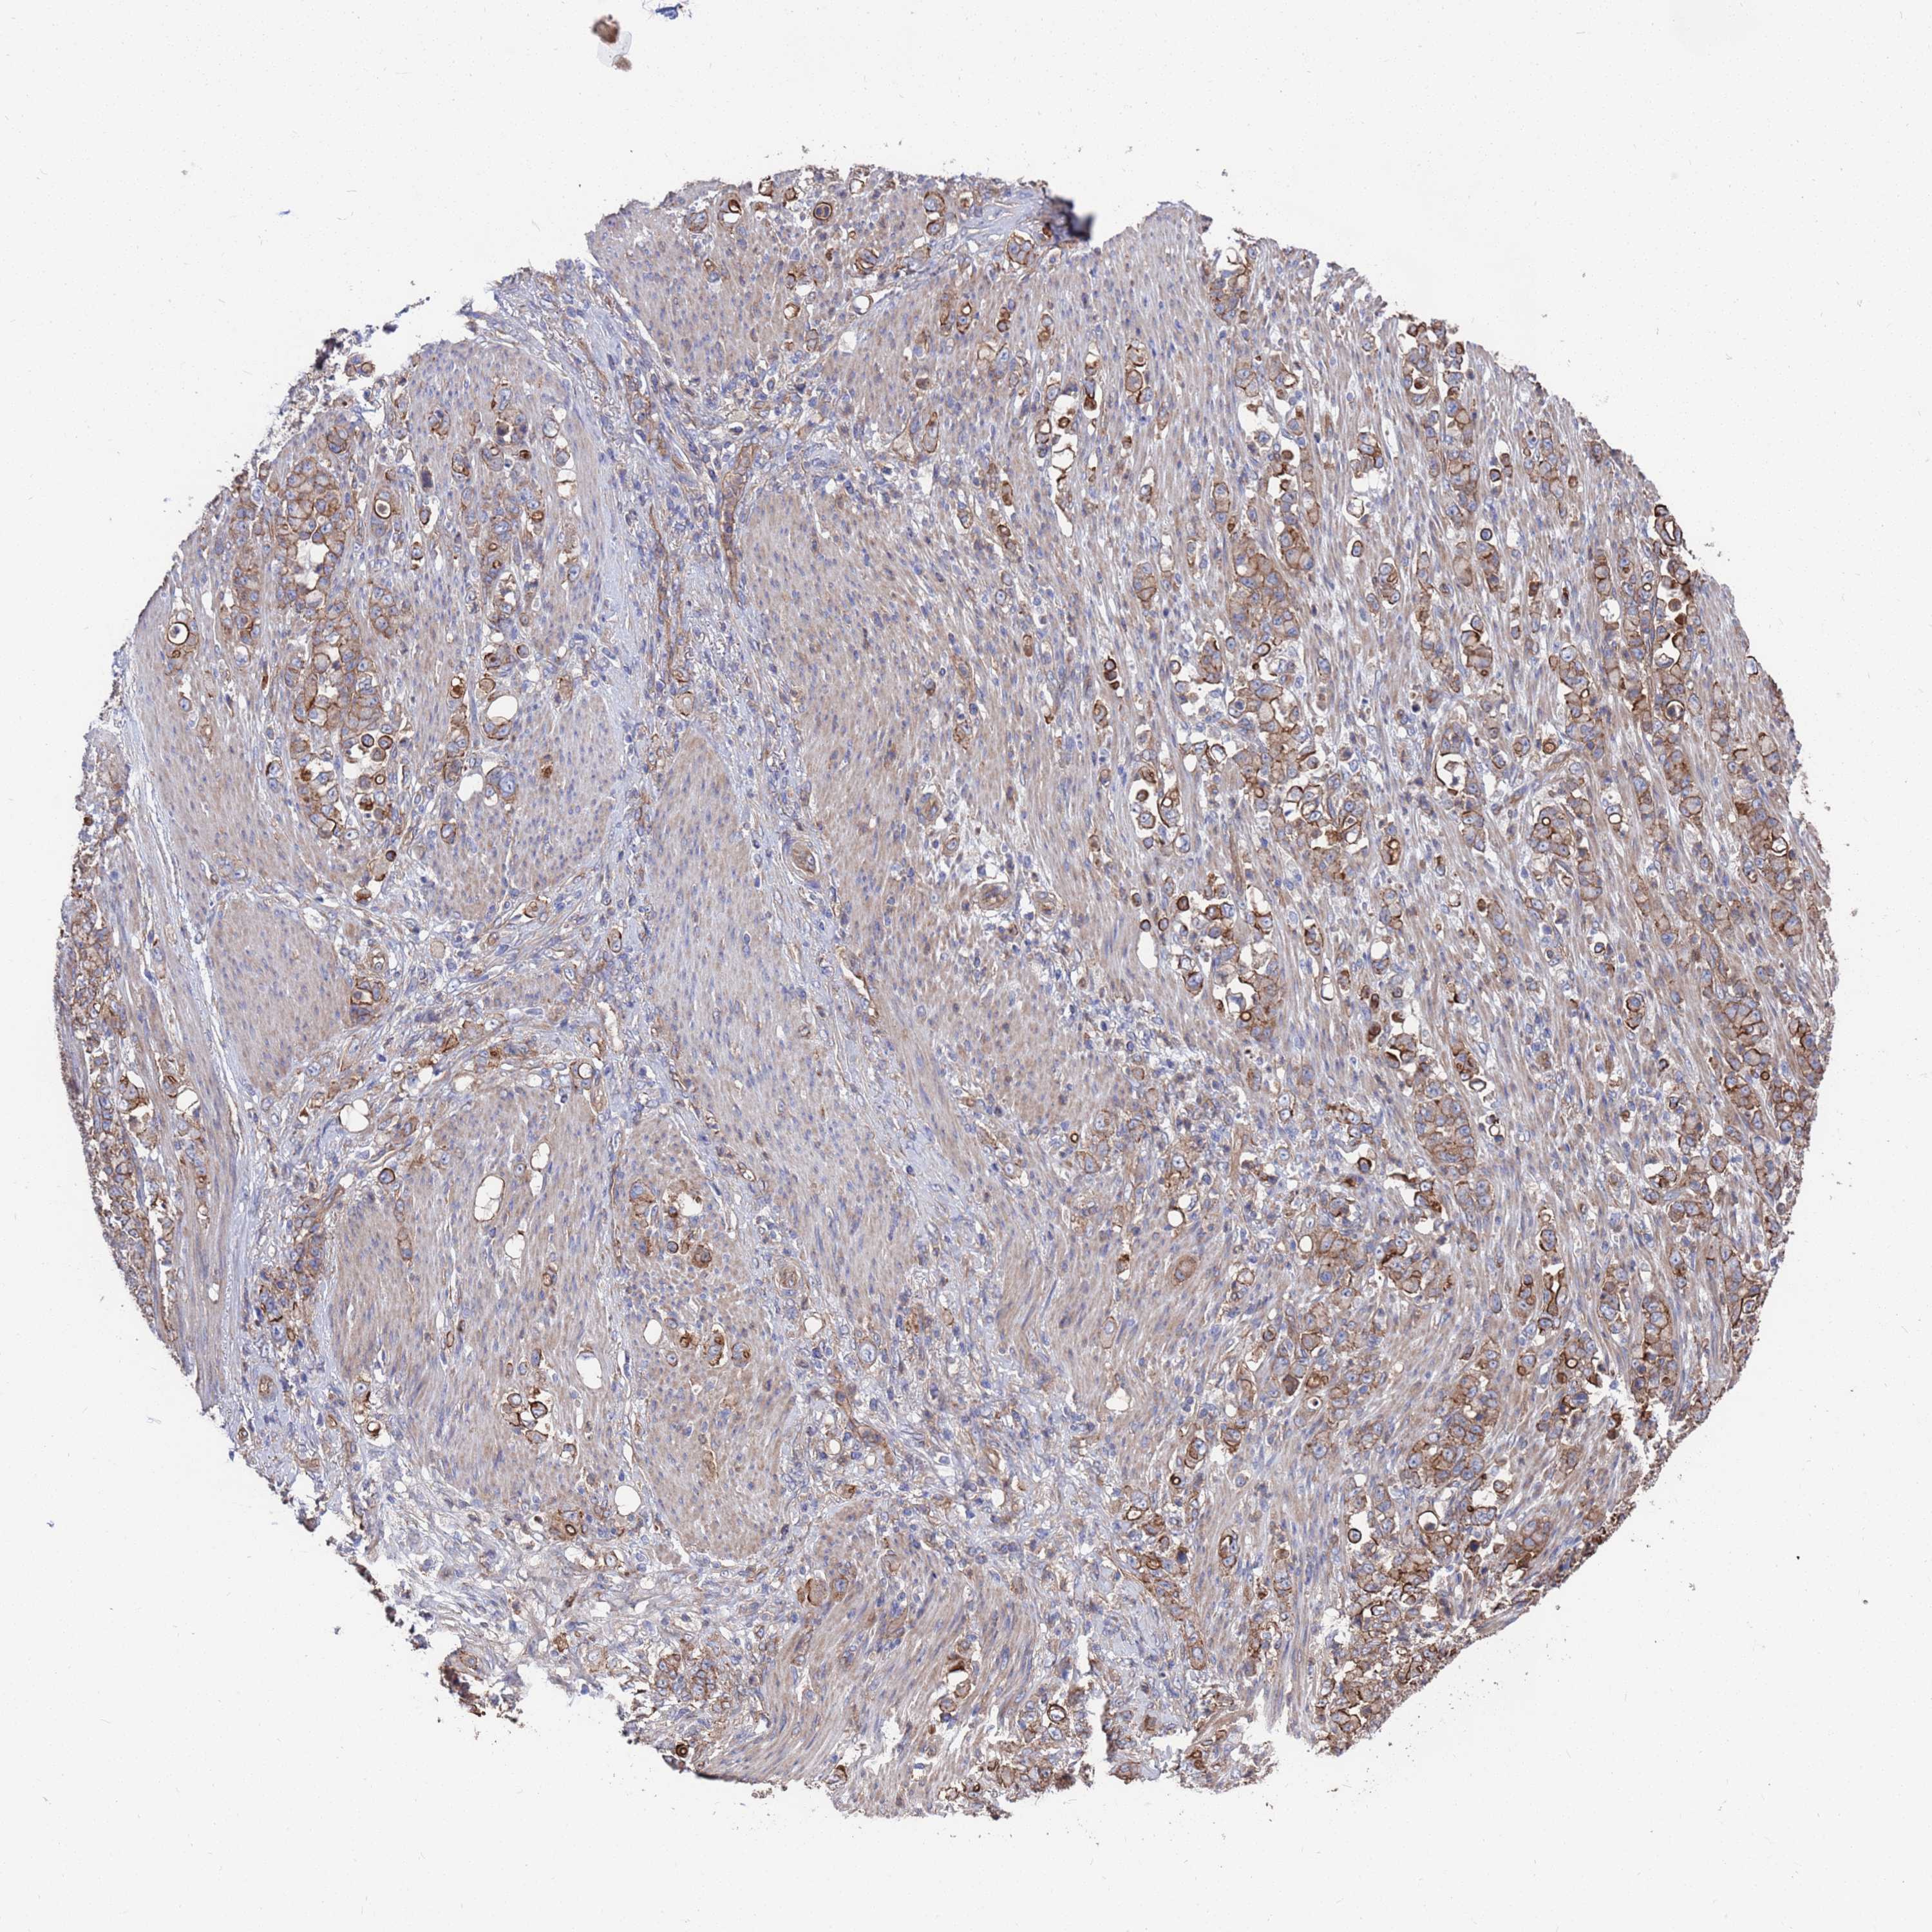

STOMACH CANCER - Protein expressioni

A mouse-over function shows sample information and annotation data. Click on an image to view it in a full screen mode. Samples can be filtered based on level of antibody staining by selecting one or several of the following categories: high, medium, low and not detected. The assay and annotation is described here.

Note that samples used for immunohistochemistry by the Human Protein Atlas do not correspond to samples in the TCGA dataset.

Antibody stainingi

Antibody staining in the annotated cell types in the current human tissue is reported as not detected, low, medium, or high, based on conventional immunohistochemistry profiling in selected tissues. This score is based on the combination of the staining intensity and fraction of stained cells.

Each image is clickable and will lead to virtual microscopy that enables deeper exploration of all samples and also displays staining intensity scores, fraction scores and subcellular localization as well as patient and tissue information for each sample.

Antibody HPA047148

Staining

High

Medium

Low

Not detected

Intensity

Strong

Moderate

Weak

Negative

Quantity

>75%

75%-25%

<25%

None

Location

Nuclear

Cytoplasmic/membranous

Cytoplasmic/membranous,nuclear

Adenocarcinoma, NOS